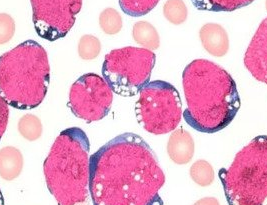

恩西地平这药专门收拾IDH2基因突变的急性髓性白血病,特别是那些R140和R172位点捣乱的癌细胞。效果嘛,对付传统化疗搞不定的复发难治病例挺管用,差不多两成患者能完全缓解,中位生存期能撑到9个月左右。

不过这药挑食得很,没IDH2突变的压根不搭理。吃药后可能闹分化综合征(发烧喘不上气)、拉肚子这些幺蛾子,得盯着点。国内暂时还买不到正版,老挝仿制药一盒1600来块倒是有渠道。简单说就是:基因检测出IDH2突变再考虑用它,效果比化疗温和,但别指望药到病除。